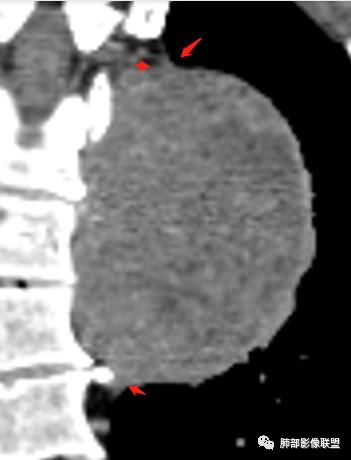

1.左上胸内脊柱旁半圆形肿块,质地坚实,密度比较均匀。

2.病灶周边见胸膜掀起,应当考虑胸壁或是纵隔来源,肺内病变不会如此。

3.降主动脉这一相对固定结构向前方推移,提示病灶相对坚实且有牢固附着点,不支持来自柔软的肺组织。

就如同在腹部,能将肾脏推移的包块,应该来自腹膜后。

4.可疑肋间动脉病供血,提示肿块来自后纵隔的可能性。

5.相邻椎间孔未见扩大,也未见块影延入椎管,易起自于神经根的鞘瘤似乎找不到相关支持点。

6.未提供矢状位骨窗图像,如在肋骨内下缘观察到压迹有助于肋间神经的鞘瘤的判断,这是因为二者之间密切的毗邻关系。

7.静脉期轻度强化,注意不是环形强化,亦未显示明确的“AB区”,神经鞘瘤与副节瘤亦未找到支持点。

综上,病灶定位胸壁或后纵隔,就发病率而言,神经源性可能性较大。